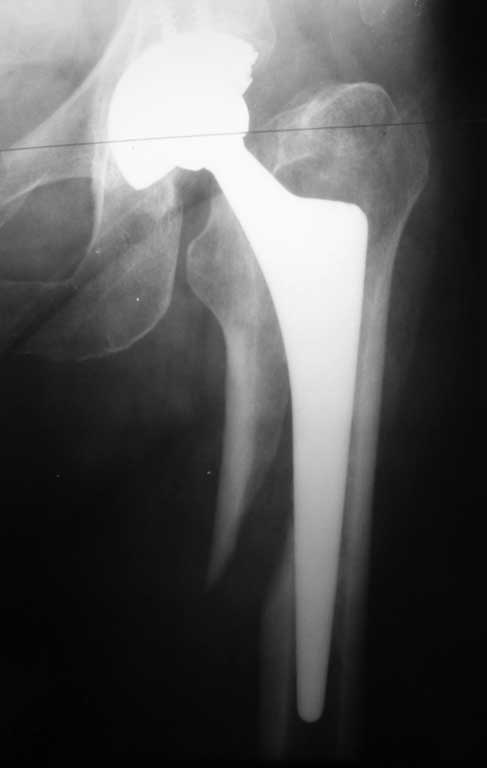

Уважаемые коллеги. Помогите определиться с тактикой лечения при перипротезном переломе

бедра. Женщина 58 лет, ранее (в марте 2010г.) оперирована в нашем отделении по поводу

перелома шейки бедра. Выполнено эндопротезирование сустава бесцементным протезом Зиммер

(чашка Трилоджи и ножка Споторно). До получения последней травмы пациентка чувствовала

себя хорошо: ходила не хромая , болей не было. 28.12.11 упала на улице. На рентгенограммах

имеется перипротезный перелом бедра в верхней трети, проседание ножки протеза. Помогите с

выбором тактики лечения. Наше мнение : ревизовать ножку на более длинную, предварительно

выполнить остеосинтез бедра серкляжами. Вот только какую ножку выбрать: цементную или

безцементную, Вагнера или Гелио (биомет) или длинную цементную ножку Экзетер(Страйкер).